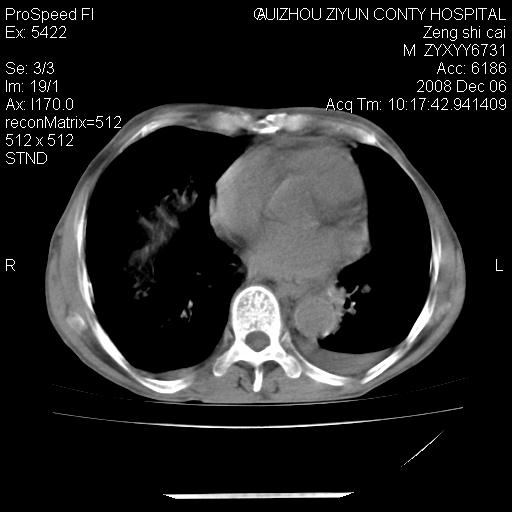

标题: CT16961:M、71岁,咳嗽半年,无血痰;胸片示右肺占位。 [打印本页]

标题: CT16961:M、71岁,咳嗽半年,无血痰;胸片示右肺占位。

右肺癌并纵隔淋巴结及胸膜转移可能性大

右肺癌并纵隔淋巴结及胸膜转移。建议气管镜

右肺纵隔型肺癌伴纵隔淋巴结及胸膜转移!

右肺纵隔型肺癌伴纵隔淋巴结转移!双侧胸水!

1)考虑右肺上叶纵隔型肺癌伴纵隔淋巴结转移。2)心包积液,双侧胸腔积液。

右肺癌并纵隔淋巴转移,腹膜后转移可能性大,两侧胸腔积液

右肺上叶纵隔型肺癌伴纵隔淋巴结转移。心包积液,双侧胸腔积液。

建议强化!主要鉴别是淋巴瘤与肺癌淋巴结转移。